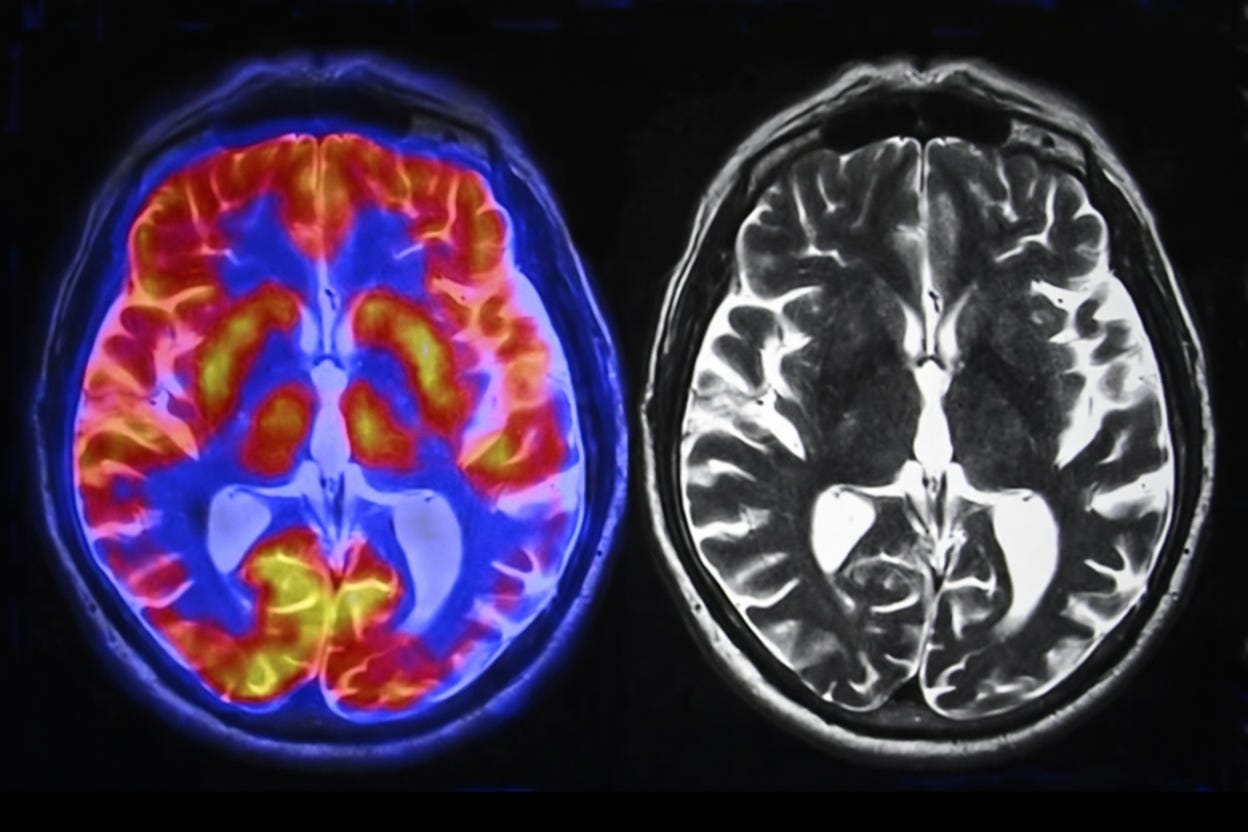

A small but growing number of studies have put people inside brain scanners or strapped EEG sensors to their heads while they use ChatGPT. Neuroimaging tools measure how things affect brain activity, so these are, potentially, the most “reliable” sources (compared to self-report surveys and behavioral testing).

Your Brain on ChatGPT, Kosmyna et al. (arXiv preprint, 2025, N=54): MIT Media Lab tracked brain activity via 32-channel EEG across four sessions over several months in three groups: ChatGPT users, Google searchers, and unaided writers. The first showed “the weakest neural connectivity,” up to 55% lower than unaided writers. They grew lazier, “resorting to copy-paste by session 3.” When switched to writing alone in session four, their brain activity stayed suppressed, which the researchers called an accumulation of “cognitive debt.” The brain-only people who used ChatGPT in session 4 showed increased brain connectivity. As Kosmyna said, “timing might be important.”

Lower engagement of cognitive control, attention, modulation networks and lower creativity in children while using ChatGPT, Horowitz-Kraus et al. (bioRxiv preprint, 2025, N=31): The only study to scan children (ages 6–7) alongside adults during chatbot interaction using fMRI. Adults showed “stronger within-network connectivity” in cognitive control networks. Children showed “lower engagement of cognitive control, attention, and modulation networks,” suggesting that kids’ brains are more affected by AI use than adults

EEG during creative design with AI tools, Wang et al. (Frontiers in Psychology, 2025, N=64): A counterpoint to the above. Design students using AI creative tools (ChatGPT, Midjourney, Stable Diffusion) showed “significantly higher concentration levels” and higher creative performance than a control group using traditional software. The difference from the MIT study: these students were actively directing AI as a creative tool vs passively receiving answers.

Effects of different AI-driven chatbot feedback on learning outcomes and brain activity, Yin et al. (Nature portfolio, 2025, N=87): Used fNIRS to measure brain activation during chatbot interaction. Different feedback types activated different brain regions. Metacognitive feedback (”Why do you think that’s the answer?”) increased activation in the “frontopolar area” and correlated with higher transfer scores. Neutral feedback activated the “dorsolateral prefrontal cortex” instead. This study essentially revealed that how a chatbot talks to you changes which parts of your brain light up.

NeuroChat: A neuroadaptive AI chatbot for customizing learning experiences, Baradari et al. (arXiv preprint, 2025, N=24): MIT Media Lab prototype that monitors EEG in real time and adjusts responses when it detects engagement dropping. “Significantly increased both EEG-measured and self-reported engagement” compared to a standard chatbot. No effect on short-term learning outcomes. Proof that “cognitive disengagement” can be fixed by building AI differently.

Conclusions: The brain imaging evidence is early: small samples, preprints, one contradictory result. But the pattern across studies points in the same direction: passive AI use (receiving answers) suppresses the brain regions involved in effortful thinking, while active AI use (directing tools, receiving challenges) can maintain or increase engagement. The variable is not the presence of AI but rather what the AI asks your brain to do: when AI does the thinking, your brain does less.